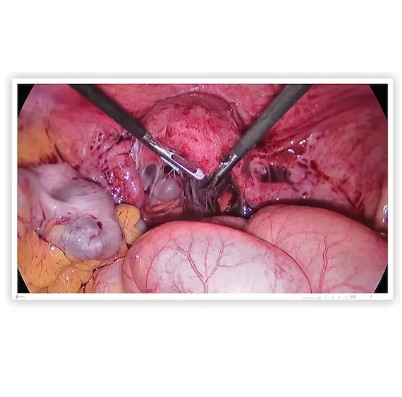

• systemy wspierające diagnostykę medyczną oraz systemy obrazowania radiologicznego